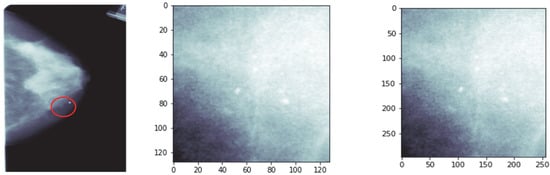

Sample images of the DDSM dataset of each category are shown in Figure 1, consisting of squared ROI images of different sizes. These images were converted to a standard size of 299 × 299, using inter-cubic interpolation algorithms, as the convolutional neural network (CNN) structure operated on images of the same size.

Figure 1.

(a) Original mammogram images taken from DDSM dataset; (b) cropped ROI images of original images; (c) resized ROI images of size 299 × 299.